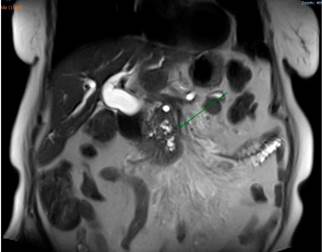

An abdominal MRI showed a dilatation of the intrahepatic and extrahepatic biliary ducts associated with a mass located in the head of the pancreas, with signs of involvement of the root of the mesentery and the presence of a focal hepatic lesion in the sixth segment of suspicious appearance (Figure 3).

Based on these findings, palliative care was decided by performing a biliary stent placement by means of an ERCP. During the procedure, the papilla was found to be distorted with local retraction of the duodenal walls, and despite cannulation of the distal bile duct was achieved, cannulation of the proximal bile duct was unsuccessful. EUS-guided biliodigestive shunt was then performed, in which a neoplastic infiltration of the duodenal papilla preventing its cannulation and a 23 mm heterogeneous hypoechoic lesion in the head of the pancreas with an up to 18 mm retrograde bile duct dilation were found (Figure 4). An initial puncture of the mass was performed for histological study purposes and then of the transduodenal bile duct with a 19 Fr. needle, which allowed the advancement of the 0.035” hydrophilic guide wire; dilatation was achieved using a biliary balloon dilator under fluoroscopic control and subsequent placement of the 10 x 80 mm fully covered metal stent was performed, which was released under endoscopic and fluoroscopic control achieving adequate opening and drainage of the contrast medium and clear bile, without subsequent complications (Figures 5 and 6). The cytology report of the samples obtained through endosonography confirmed adenocarcinoma involvement. Two months later, a total bilirubin control was performed obtaining the following results: total bilirubin: 2.42 mg/dL; direct bilirubin: 1.85 mg/dL, and indirect bilirubin: 0.58 mg/dL (Figure 7). Palliative care was continued in the oncology service.